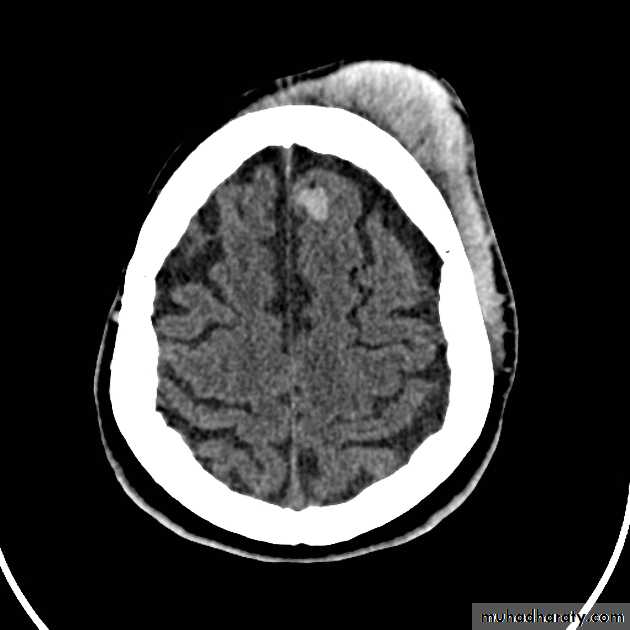

Common CT findings of traumatic brain injury